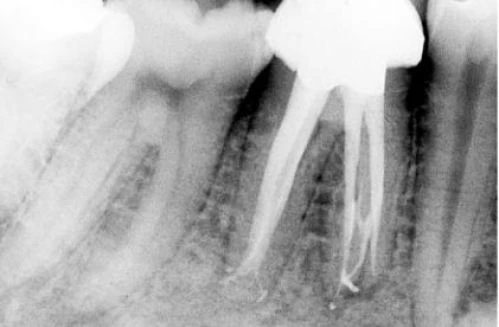

–  Trong 35% trường hợp có sự hiện diện của 4 ống tủy. Chân xa có 2 ống tủy, 1 ở phía ngoài và 1 ở phía trong (hình 11.109).

–  Ống tủy xa thứ 2 thỉnh thoảng được thấy ở 1 chân riêng biệt ở phía xa trong. Nó hơinhỏ hơn và nằm ở phía gần chân răng xa ngoài (hình 11.110).

Hình 11.109. A. Phim sau điều trị của  RCL 1 dưới. B. Nhìn theo chiều gần xa trên cùng răng đó có thể thấy có 2 ống tủy ở chân xa, các ống tủy chân gần mặc dù gặp nhau ở 1/3 giữa nhưng vẫn có 2 lỗ chóp. C. Xoang tủy ở R36 với 2 ống tủy ở chân gần và 2 ống tủy ở chân xa. D.Trong trường hợp răng cối lớn dưới khác cũng có 4 ống tủy, mỗi ống tủy có 1 lỗ chóp riêng.

Hình 11.110. A. Một vùng hơi cản quang trong vùng chẽ R36 vì chân xa ngoài. Dễ dàng nhận ra phần laminadura bao quanh chân răng này và hình ảnh ống tủy. B. Hình ảnh răng cối lớn một dưới sau khinhổ ra. C. Phim sau điều trị R46 với 2 chân xa và 2 ống tủy xa.